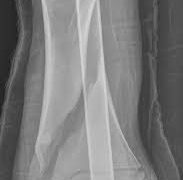

後肢の中足骨以下と前肢の中手骨以下の骨の骨折は、原因、診断、治療など、いずれもほぼ同様ですのであわせて記述することにします。大動物中足骨および中手骨の骨折 大動物では非常にしばしば発生します。牛では、中足骨の骨折が骨折の17.5%、中手骨の...